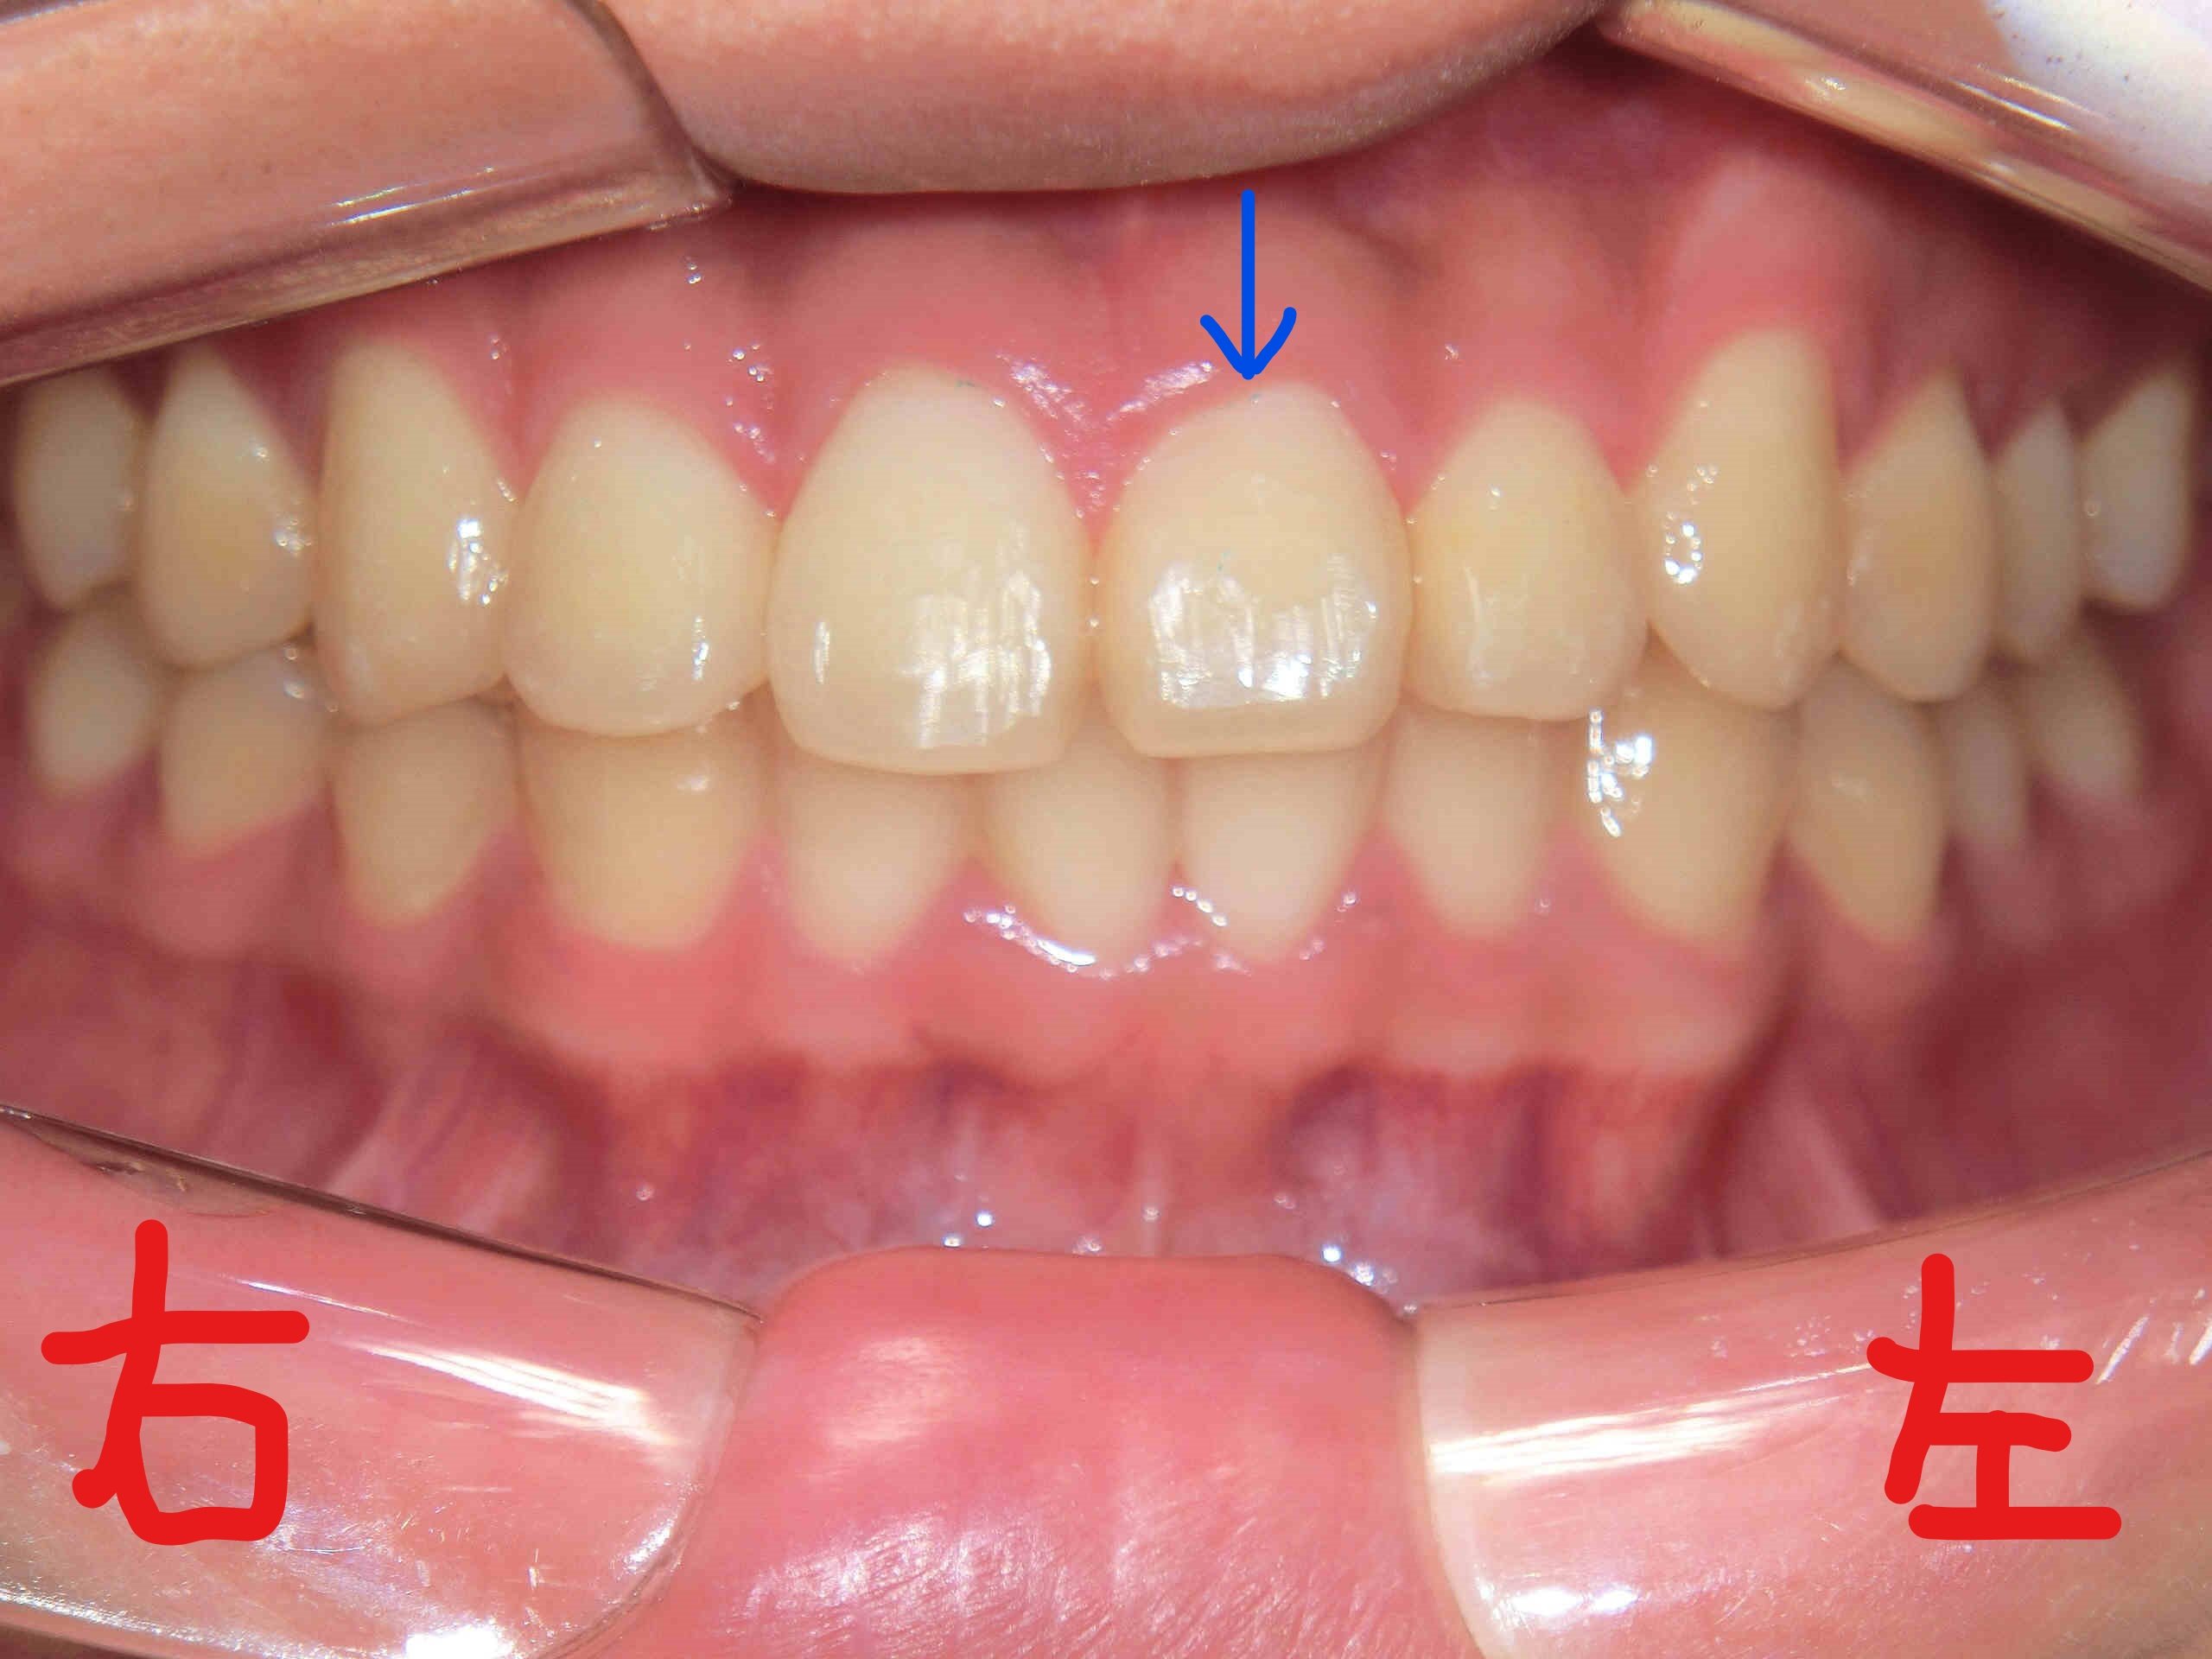

上段の写真が矯正開始前、下段の写真が矯正終了直後のものです。

次に、左上がブラケットを撤去する直前の上顎を下から見上げた写真、右上がブラケット撤去直後の写真です。青色矢印の歯にご注目ください。左上の前歯の捻転がしっかりと改善されているのがお分かりいただけると思います。